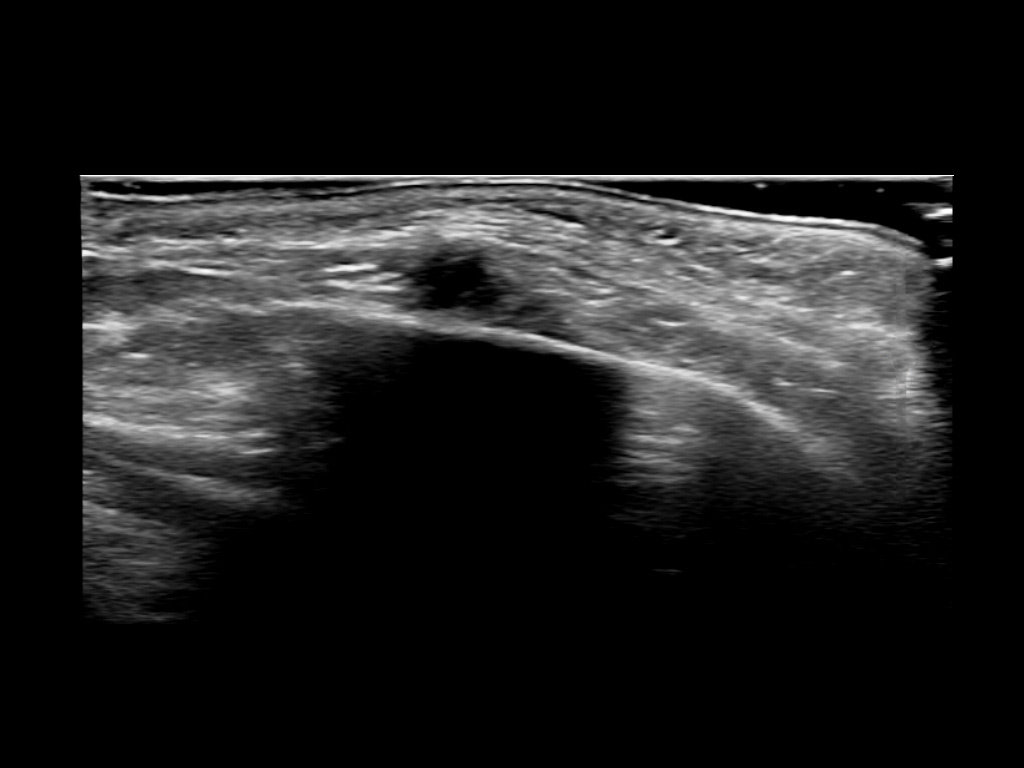

PCL 0

PCL 10a

PCL 11a

PCL 12a

PCL 13a

PCL 14a

PCL 15a

PCL 16a

PCL 1a

PCL 2a

PCL 3a

PCL 3b e

PCL 4a

PCL 4b e

PCL 5a

PCL 5b e